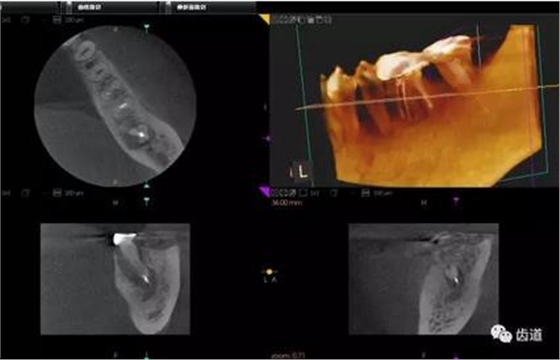

1、上頜尖牙阻生

上頜尖牙埋伏阻生在CBCT中的影像